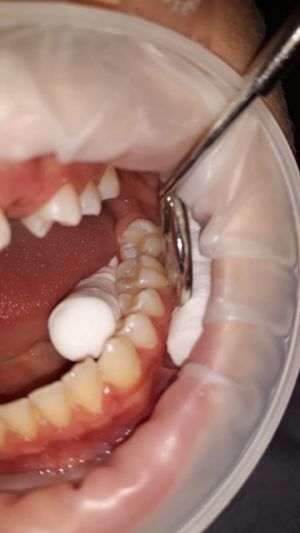

- 3. la sigillatura si effettua utilizzando una resina composita fluida che viene applicata nei solchi dei denti per mezzo di un dispenser oppure di un apposito pennellino. La resina è di colore bianco o trasparente e da fluida viene trasformata in solida grazie all'utilizzo di una lampada definita fotopolimerizzante.